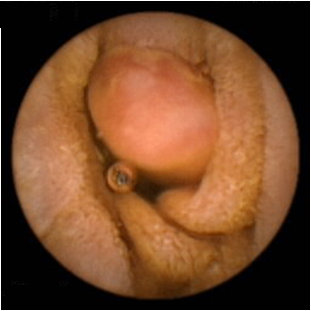

⑦超声胃镜

EUS是将微型高频超声探头安置在内镜前端,在内镜直视观察腔内形态的同时,又可进行实时超声扫描近距离探查,使靶器官的结构与图像更为清楚,为临床治疗方案的选择提供了有力的支持。我院消化内镜于2004年在四川省率先开展EUS新技术,目前拥有国内最新—代的EUS系统,它集超声内镜主机、高频小探头、三维超声探头、环扫内镜超声等 先进设备为—体。我院EUS诊疗组,现有教授1名、副教授2名,每年完成近千例消化道EUS诊疗,EUS诊疗技术达到省内先进水平。

正常食道

食道平滑肌瘤

食道粘膜肌层平滑肌瘤

异位胰腺

脂肪瘤

间质瘤

胰头癌

胆总管结石

为什么需要EUS

普通内镜检查只能发现消化道表面的病灶,通过EUS显示消化管壁层次结构及周围脏器病变,能更准确判断胃肠隆起病变的 性质、来源、肿瘤的浸润深度,还能取活检,指导确定治疗方案及判断疗效。